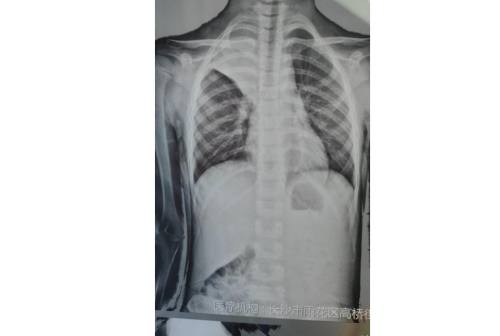

)驻点该社区的儿科专家、副主任医师余庆乐仔细询问了病史,并做了详细的体格检查,发现患儿右肺呼吸音明显偏低,完善胸片检查后发现星星整个右上肺不张,根据经验高度怀疑为肺炎支原体肺炎,并且很有可能出现了塑形支气管炎、痰栓堵塞等肺内并发症,需要尽快转上级医院住院治疗。

余庆乐一边安抚家长情绪,一边联系自己所在医院的儿科,让孩子从社区尽快转诊到医院。医院有专人接诊,快速安排了孩子住院,当天下午就进行了纤维支气管镜检查及治疗,镜下明显看到形似“树枝”状胶冻样分泌物,肺炎支原体抗体结果回报阳性,也证实了孩子感染了肺炎支原体肺炎,经过积极对症治疗后,星星终于康复出院,王女士悬着的心也终于落地了,出院后马上找到高桥街道卫生服务中心,对余庆乐医生当面表示感谢。